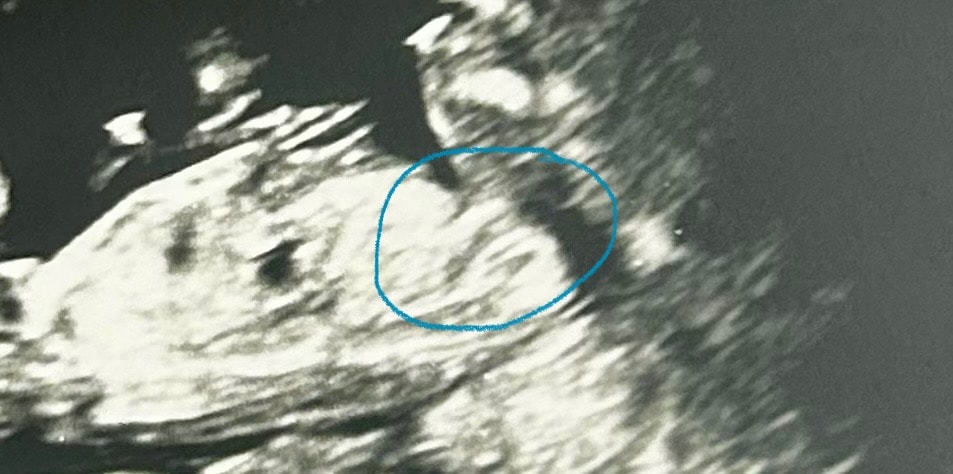

На 1 скрининге дали фоточку малявочки.

Я же верно понимаю, что это половой бугорок? Знаю, что у мальчиков и девочек он особо еще не отличается.

Нет, полового бугорка у вас не видно

Вот тут видно ☝️ и это мальчик, хотя если судить по бугорку, это девочка)